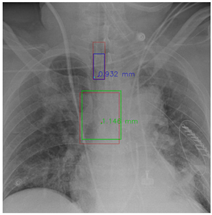

Figure 7 and Figure 8 demonstrate the effect of post-processing. The red bboxes and points in these figures are the GT ETT/bifurcation bboxes and the position of GT ETT tip/Carina, respectively. The green polygon is the GT mask of the ETT and the bifurcation. The blue bbox and point are the predicted ETT bbox and ETT tip, respectively. The yellow bbox and point are the predicted bifurcation and Carina, respectively. Specifically, without the post-process, the model might leave more than one predicted ETT tip/Carina, such as where the red arrow points in Figure 7a. However, with the post-process, the extra points would be removed as shown in Figure 7b. Besides, with the refinement process in the post-process, the feature point of ETT tip/Carina could be further refined as shown in Figure 8. Concretely, the object error of Carina was corrected from 8.469 mm to 1.319 mm.

Figure 7.

Ensuring at most one ETT tip/Carina left. (a) Without post-process. (b) With post-process.